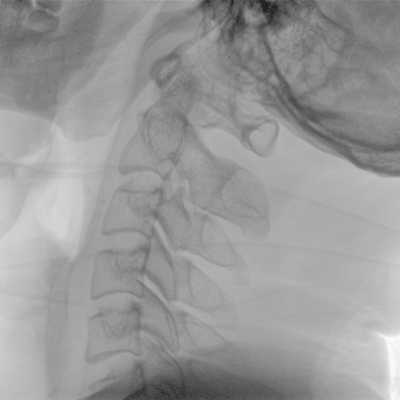

可用于常規(guī)的外周血管介入手術,設備的移動性好,對手術室空間要求低,可滿足長時間X光透視的需求,且增加了獨特的血管影像處理功能,是開展介入手術的理想設備。

優(yōu)質平板探測器、可靈活升降調節(jié)SID、獨特圖像處理系統(tǒng)、高品質濾線柵,大視野成像清晰不失真。

采用智能劑量控制技術,可根據(jù)不同體型和不同部位,準確調節(jié)投照劑量。使操作者在任何使用環(huán)境下,都能實現(xiàn)低劑量、診視圖像清晰的效果。